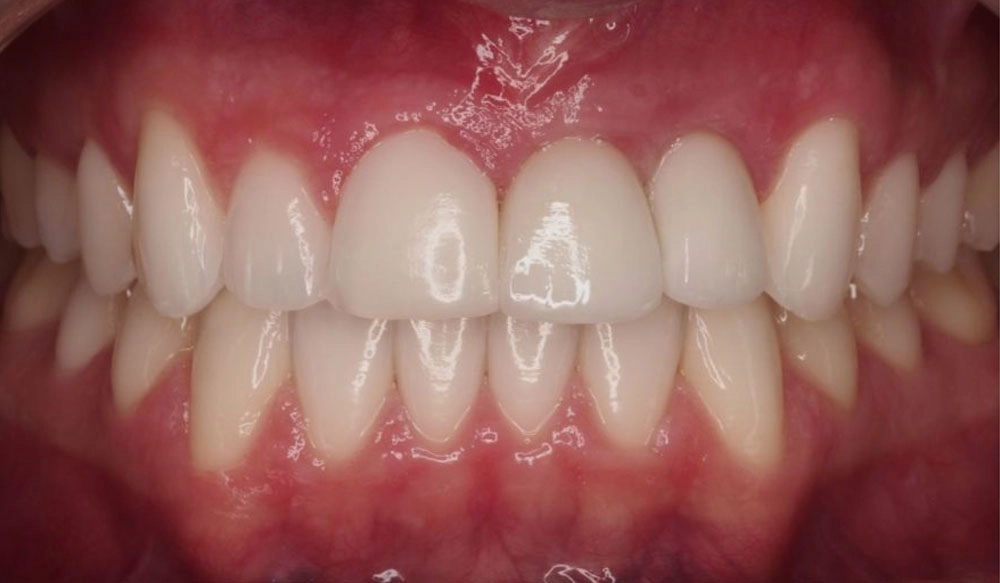

Làm răng đều hơn

Một số nụ cười không hề có bất kỳ "vấn đề" nào cả — nhưng những sửa chữa nhỏ có thể tạo ra sự khác biệt lớn trong cuộc sống của bệnh nhân. Với phương pháp điều trị Invisalign®, bệnh nhân của bạn giờ đây có thể có được nụ cười mà họ yêu thích nhanh hơn tới 50 phần trăm. 1 2

Thông tin bệnh nhân:

Tuổi: 62

Giới tính: Nữ

Lựa chọn điều trị Invisalign: Invisalign toàn diện

Tổng thời gian điều trị:

13 tháng